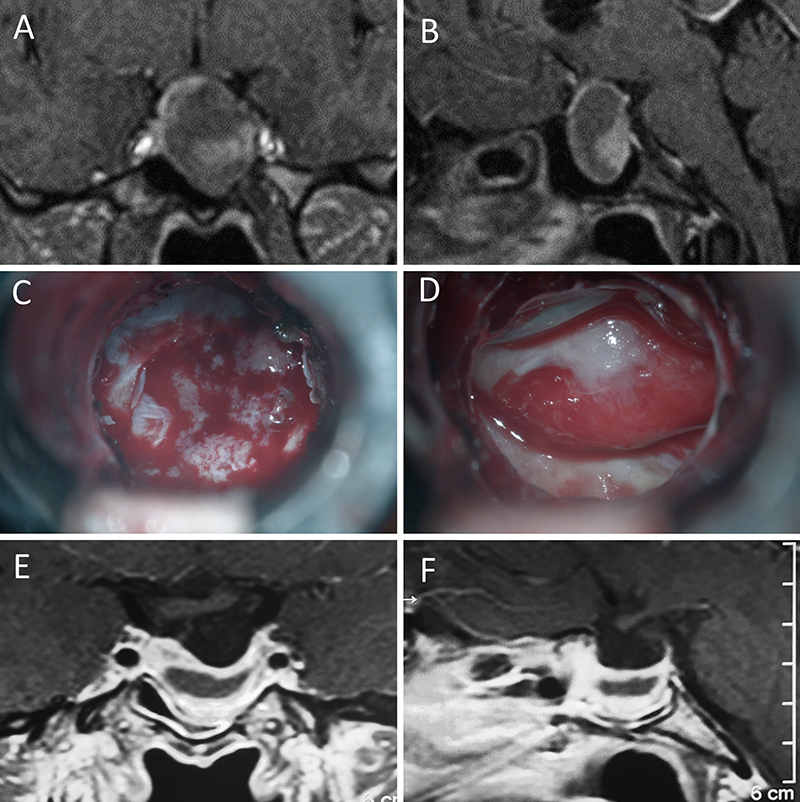

Figura 7: Acromegalia en mujer de 39 años. Con remisión bioquímica tras la cirugía. A-B: RM preoperatoria; C-D: intraoperatorio; E-F: RM postoperatoria.

Figura 8: Acromegalia en mujer de 50 años. Con remisión bioquímica tras la cirugía. A-B: RM preoperatoria; C-D: intraoperatorio; E-F: RM postoperatoria.